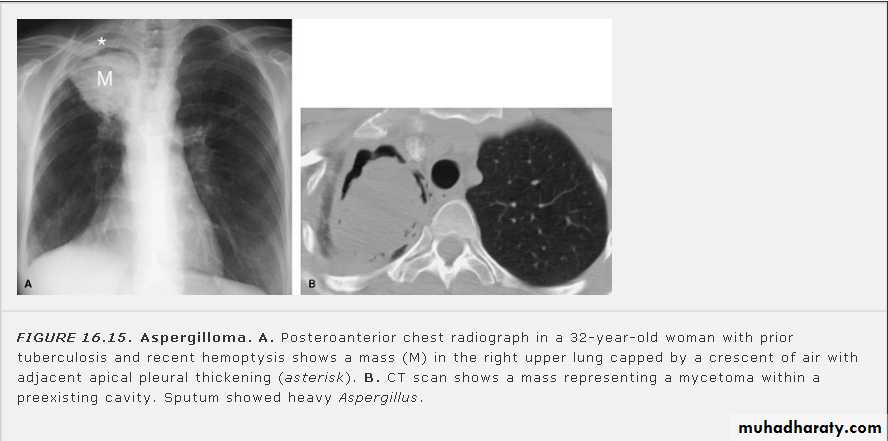

Fungus ball (air crescent sign)

Un complicated Hydatid cyst of th lung , cuased by echenococus granulosis seen as well defined nodule or mass lesion .

Early rupture is sen as a cresnt air sign .ddx aspergillus ball